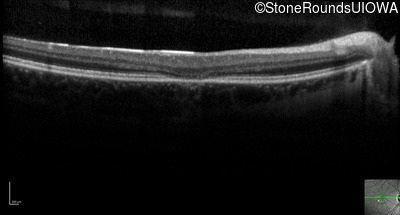

Optical Coherence Tomography - Right - 20/20 -2 sc

Exemplar / OCT Stack